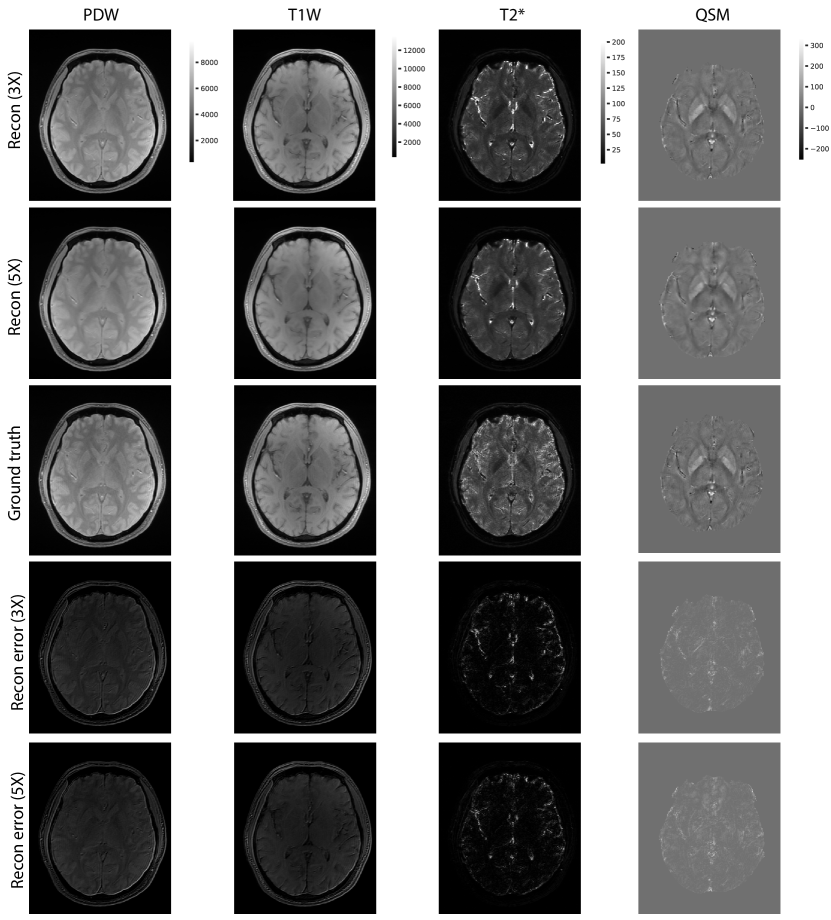

Figure 2 shows the examples of reconstructed MULTIPLEX echo images from the test dataset. The reconstruction results at 3X acceleration are quite similar to the ground truth, while the results at 5X acceleration show relatively worse reconstruction quality. Compared to the ground truth, the DL reconstructions have less ringing artifacts and noise. Table 1 shows the quantitative results for the reconstructed echo images at 3X and 5X accelerations, which are consistent with the visual examples in Figure 2. Based on the reconstructed echo images, we also calculated the parametric images such as PDW, T1W, T2* and QSM (Figure 3 and Table 2), which are also similar to the ground truth results.

Then the DL reconstructed echo images were processed to generate the following parametric images: (1) Composite PDW and T1W: by averaging all the echo images from FA1 or FA2, respectively. (2) T2* mapping: calculated using MDI method (Ye and Lyu, 2019) on multi-echo images (3) QSM: the field map was first extracted from multi-echo images (Ye et al., 2019b), and was then used to generate QSM using the L2-norm optimization method with dynamic streaking artifact regularization (Ye et al., 2019a).